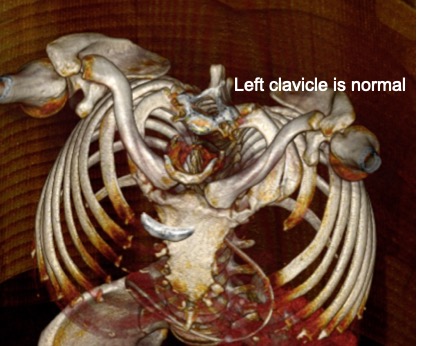

Poland’s Syndrome-CT - Sumer’s Radiology Blog

www.indianradiology.comsyndrome radiology

www.indianradiology.comsyndrome radiology

Poland Syndrom - Poland Syndrome | Radiology Case | Radiopaedia.org

srknlyjsjtnat.blogspot.comСиндром. Поланда синдром (Poland Syndrome). + | Портал радиологов

srknlyjsjtnat.blogspot.comСиндром. Поланда синдром (Poland Syndrome). + | Портал радиологов